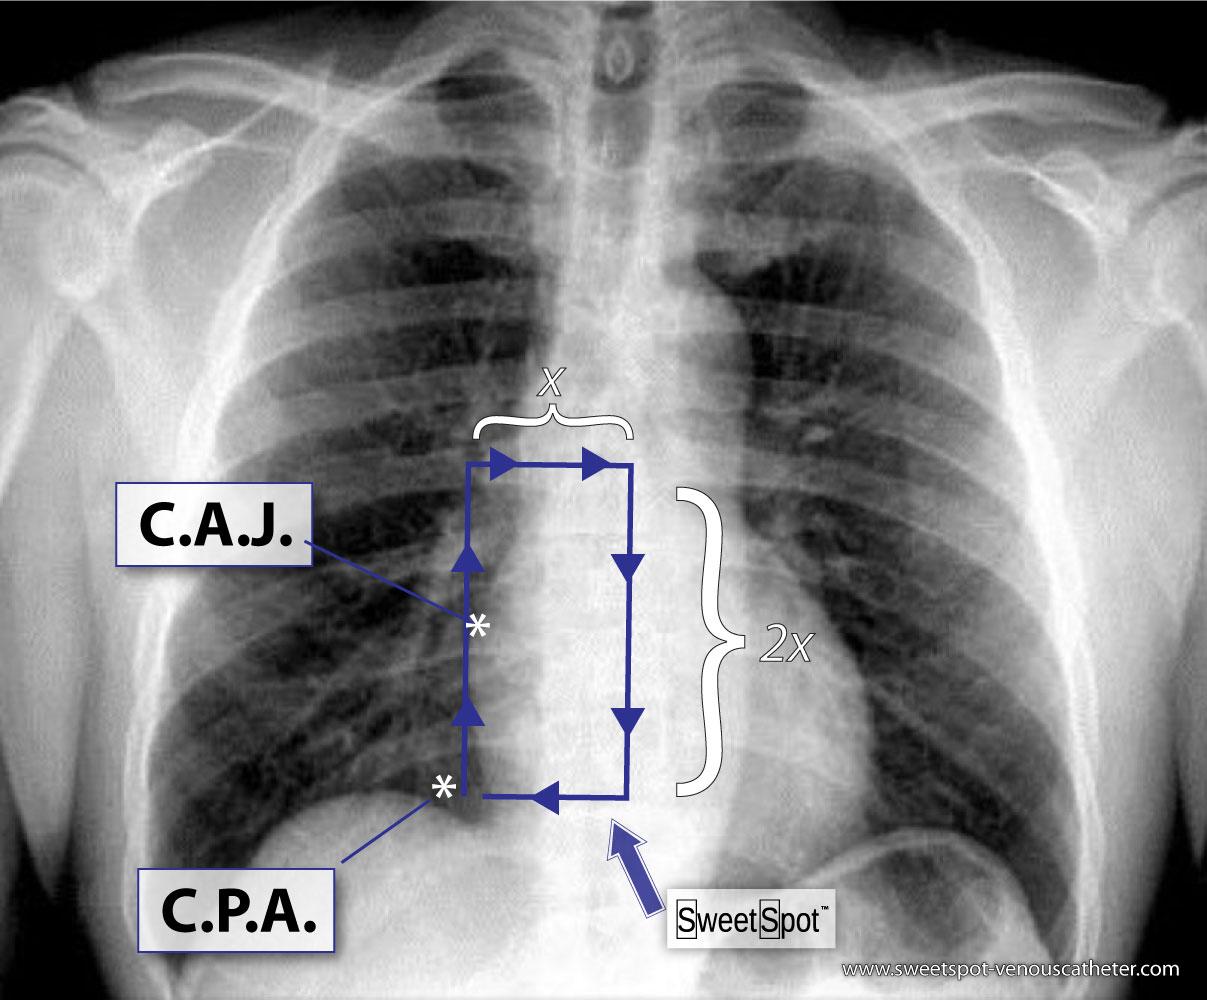

1. When I place a VAD under flouroscopic visualization, my optimal tip position is in the bottom of the box at expiration. See Fig.# 25 - Gallery.

2. On inspiration upright CXR, the tip of VAD is ideally at C.A.J. See Fig.# 09 - Gallery.

CXR Sweet Spot™ Box Measurements

CXR Sweet Spot™ Box

8. Even on normal frontal chest x-rays, there can be significant variation in the appearance of the cardiomediastinal silhouette which can result in slight subjectivity in the exact location of the margins of the SWEET SPOT™. The closer the catheter tip is to the cavoatrial junction, the less this matters.